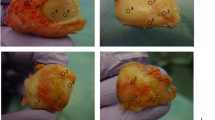

A 61-year-old man who had previously undergone meniscectomy in the right knee. He had pain on the inside of the right knee while walking and was being given oral analgesics treatment and injections by his local physician. However, the patient showed no improvement and was referred to our department for further examination. The patient was subsequently diagnosed with osteoarthritis of the right knee and underwent high tibial osteotomy (Figure 5).

DT imaging in the severe cartilage damage. The patient underwent surgery for a right knee medial meniscus injury. Outerbridge grade 3 cartilage damage caused by the medial meniscus rupture was observed throughout the entire inner femoral condyle. The ADC for this area was measured as 2.15 × 10−3 mm2/s.